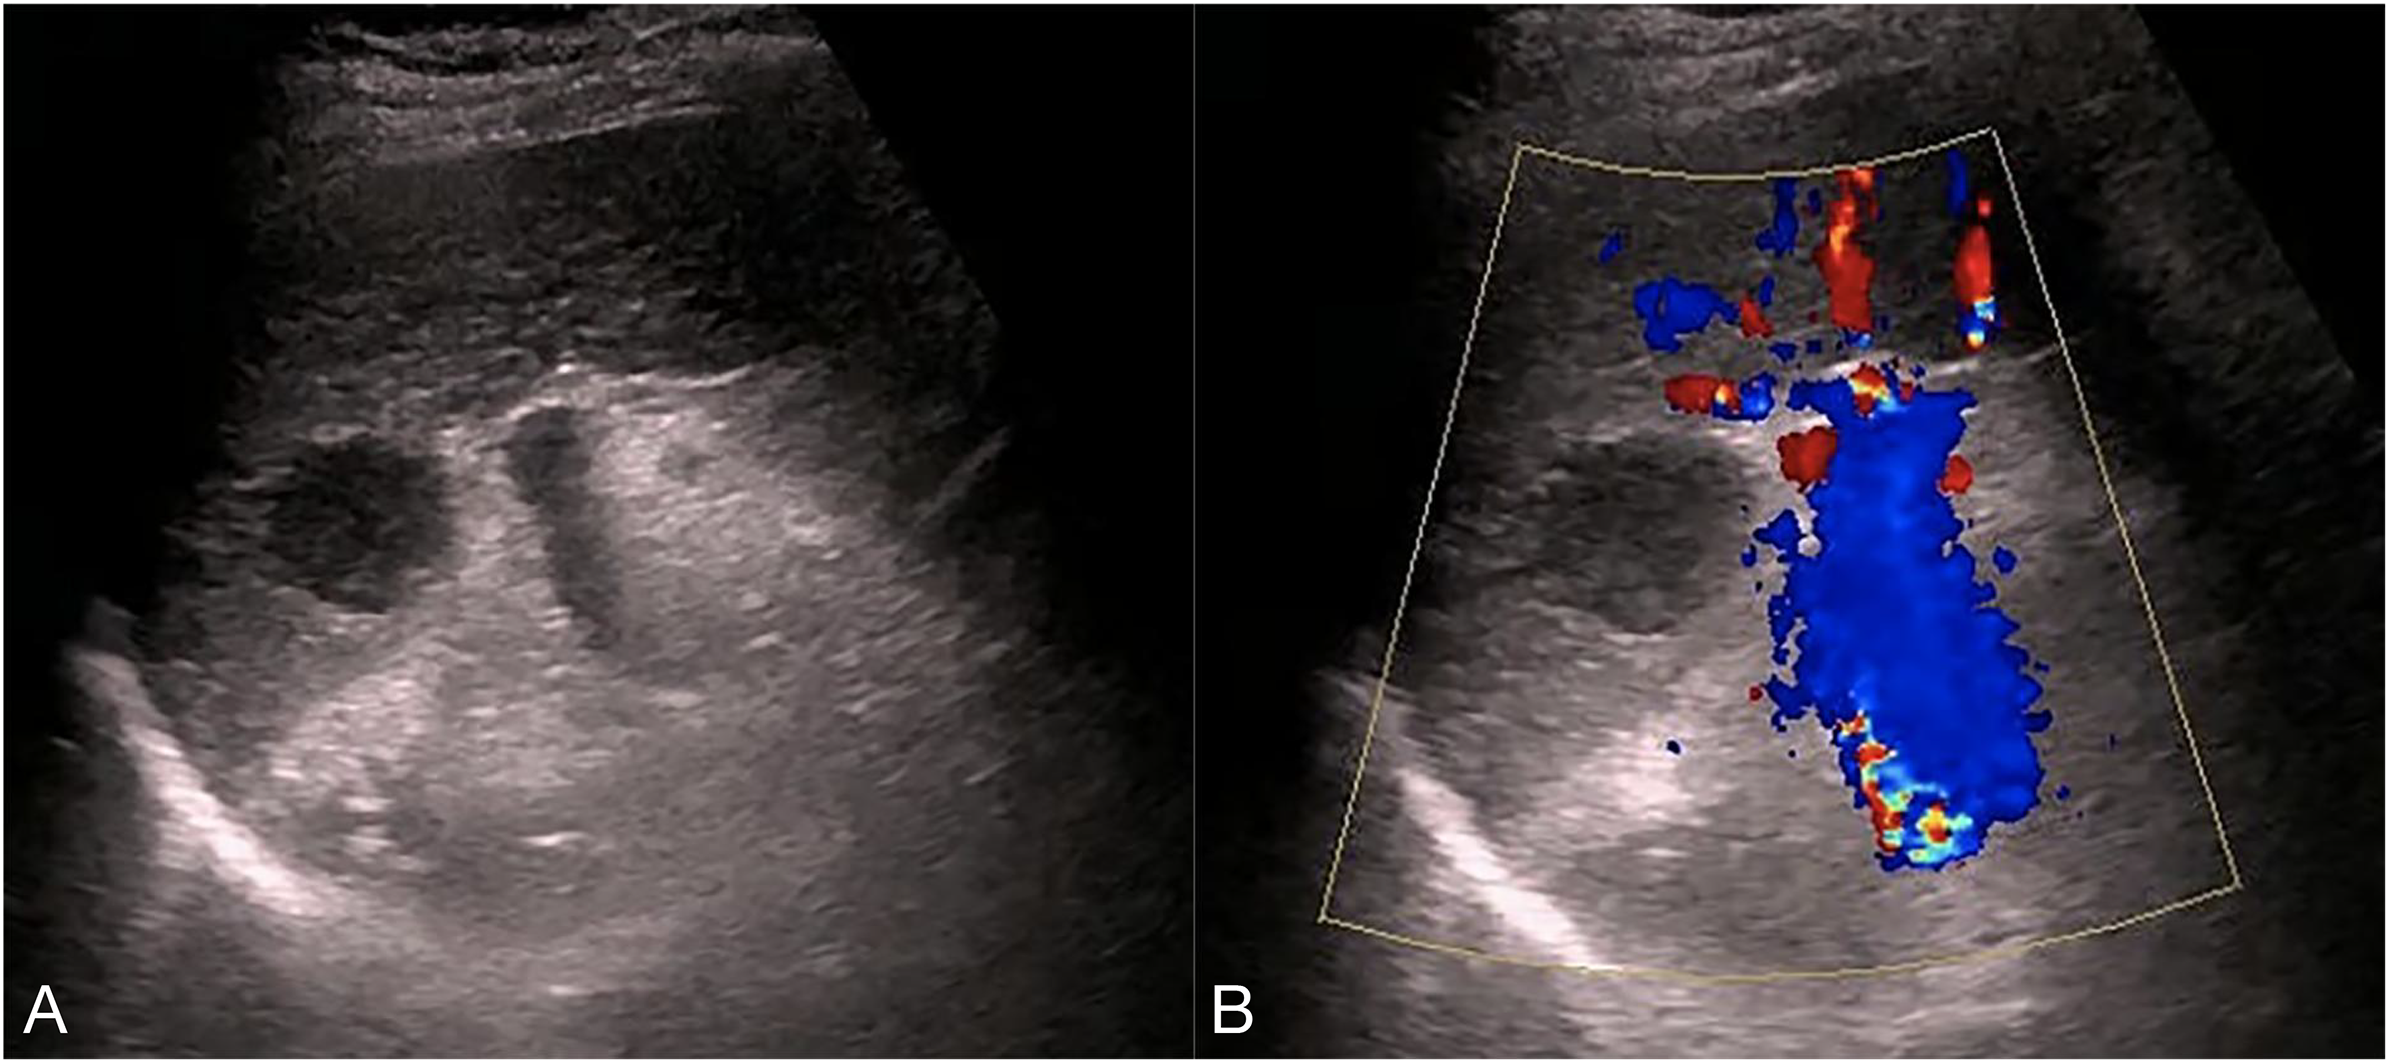

Ultrasonography conducted 2 years ago showed an enlarged spleen with 42 mm thickness and 145 mm length. The splenic parenchyma exhibited a diffusely thickened echotexture with a reticular pattern and no space-occupying lesions were identified. Two-dimensional ultrasonography conducted in our hospital showed an enlarged spleen, with approximately 52 mm thickness and 147 mm length, diffuse thickening and uneven distribution of the splenic parenchymal echo, and zonal or grid-shaped. A mass of size approximately 24 × 22 mm was detected at the hilum of the spleen. It showed irregular surface, with a very low internal echo, oval shape, and clear boundary. Color Doppler flow imaging revealed a weak blood flow signal in the mass located at the splenic hilum, with no apparent abnormality in the blood flow signal in the spleen (Figure 1). To further qualitatively diagnose the mass located at the splenic hilum, CEUS was performed after receiving patient consent. Following the infusion of the contrast agent SonoVue, the mass located at the splenic hilum began to show inhomogeneous enhancement (low enhancement) in the arterial stage, with a clear enhanced edge. The enhancement reached the peak at 17 s, and the peripheral splenic tissue showed enhanced uniformity as compared to the mass. At the venous stage, the mass began to show a decline in enhancement at 24 s. Compared to the peripheral splenic tissue, regression of the tumor mass was delayed, and the overall enhancement pattern was slow-in and fast-out, as shown in Figure 2. Combined with the results of CEUS, the final diagnosis was splenomegaly with splenic lymphoma. Needle biopsy was recommended if necessary. CT imaging revealed an enlarged spleen with uneven distribution; two isodense enhanced foci were observed in the spleen, with the larger one showing a diameter of approximately 20 mm (Figure 3). Bone marrow aspiration showed the following pathological findings: CD20(+; a small number of B lymphocytes), CD3(−), CD138(−), and CD38(−). Bone marrow hyperplasia was slightly reduced.

Figure 1. Two-dimensional ultrasound and Color Doppler flow images. (A) the spleen was enlarged, with approximately 52 mm thickness and 147 mm length, diffuse thickening and uneven distribution,of the parenchymal echo, and zonal- or grid-shaped. A mass was observed at the splenic hilum, with a size of approximately 24 × 22 mm, uneven surface, very low internal echo, oval shape, and clear boundary. (B) The mass at the splenic hilum showed a weak blood flow signal, with no apparent abnormality in the blood flow signal of the spleen.